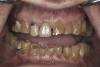

(7.) Preoperative anterior, open view. Note the significant amount of wear, erosion, and abfraction lesions.

Figure 7

(10.) Preoperative anterior, closed view. Note the end-to-end occlusion of the anterior teeth and the wear on the incisors and centrals resulting in no anterior or canine guidance.

Figure 10